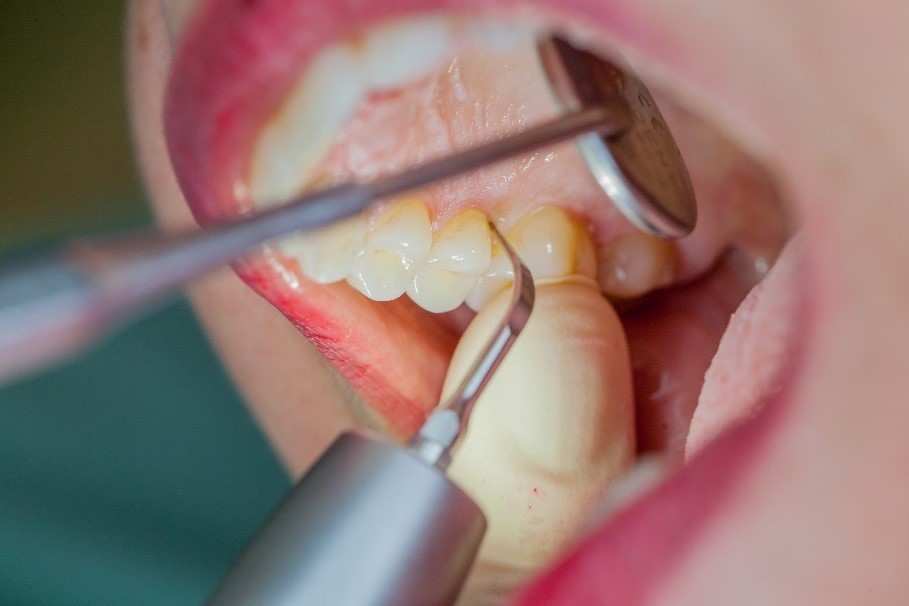

Where necessary, initial periodontal treatment is carried out. First, professional tooth cleaning establishes healthy gingival conditions. In this procedure, calculus (Fig. 1) and biofilm (Fig. 2) are removed as far as the gingival sulcus. In combination with careful instruction on oral hygiene, this gives the patient the basis for long-term freedom from inflammation.15